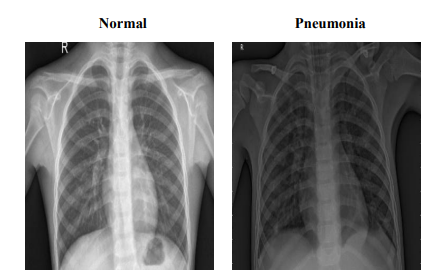

The Pneumonia dataset comprises 5,860 chest X-ray JPEG images, categorized into 'Pneumonia' and 'Normal' conditions, derived from pediatric patients aged one to five years at the Guangzhou Women and Children’s Medical Center. This dataset has undergone extensive quality control, with each image being rigorously screened for clarity and subsequently diagnosed by two expert physicians, with additional evaluations by a third expert for the validation subset. The images are organized into 'train', 'test', and 'valid' folders to facilitate efficient data access and model training. Figure 2 provides representative images from the dataset, illustrating the visual differences between 'Pneumonia' and 'Normal' conditions. These samples highlight the dataset's clarity and diagnostic quality, which are crucial for enhancing model accuracy. The training set includes 5,214 images (1,340 Normal, 3,874 Pneumonia), the testing set comprises 624 images (234 Normal, 390 Pneumonia), and the validation set contains 16 images evenly divided between Normal and Pneumonia (8 each). This structured organization ensures the dataset's suitability for developing robust diagnostic models, enabling detailed study and effective management of pediatric pneumonia through advanced machine learning techniques.

Figure 2: Sample Images from Pneumonia Dataset